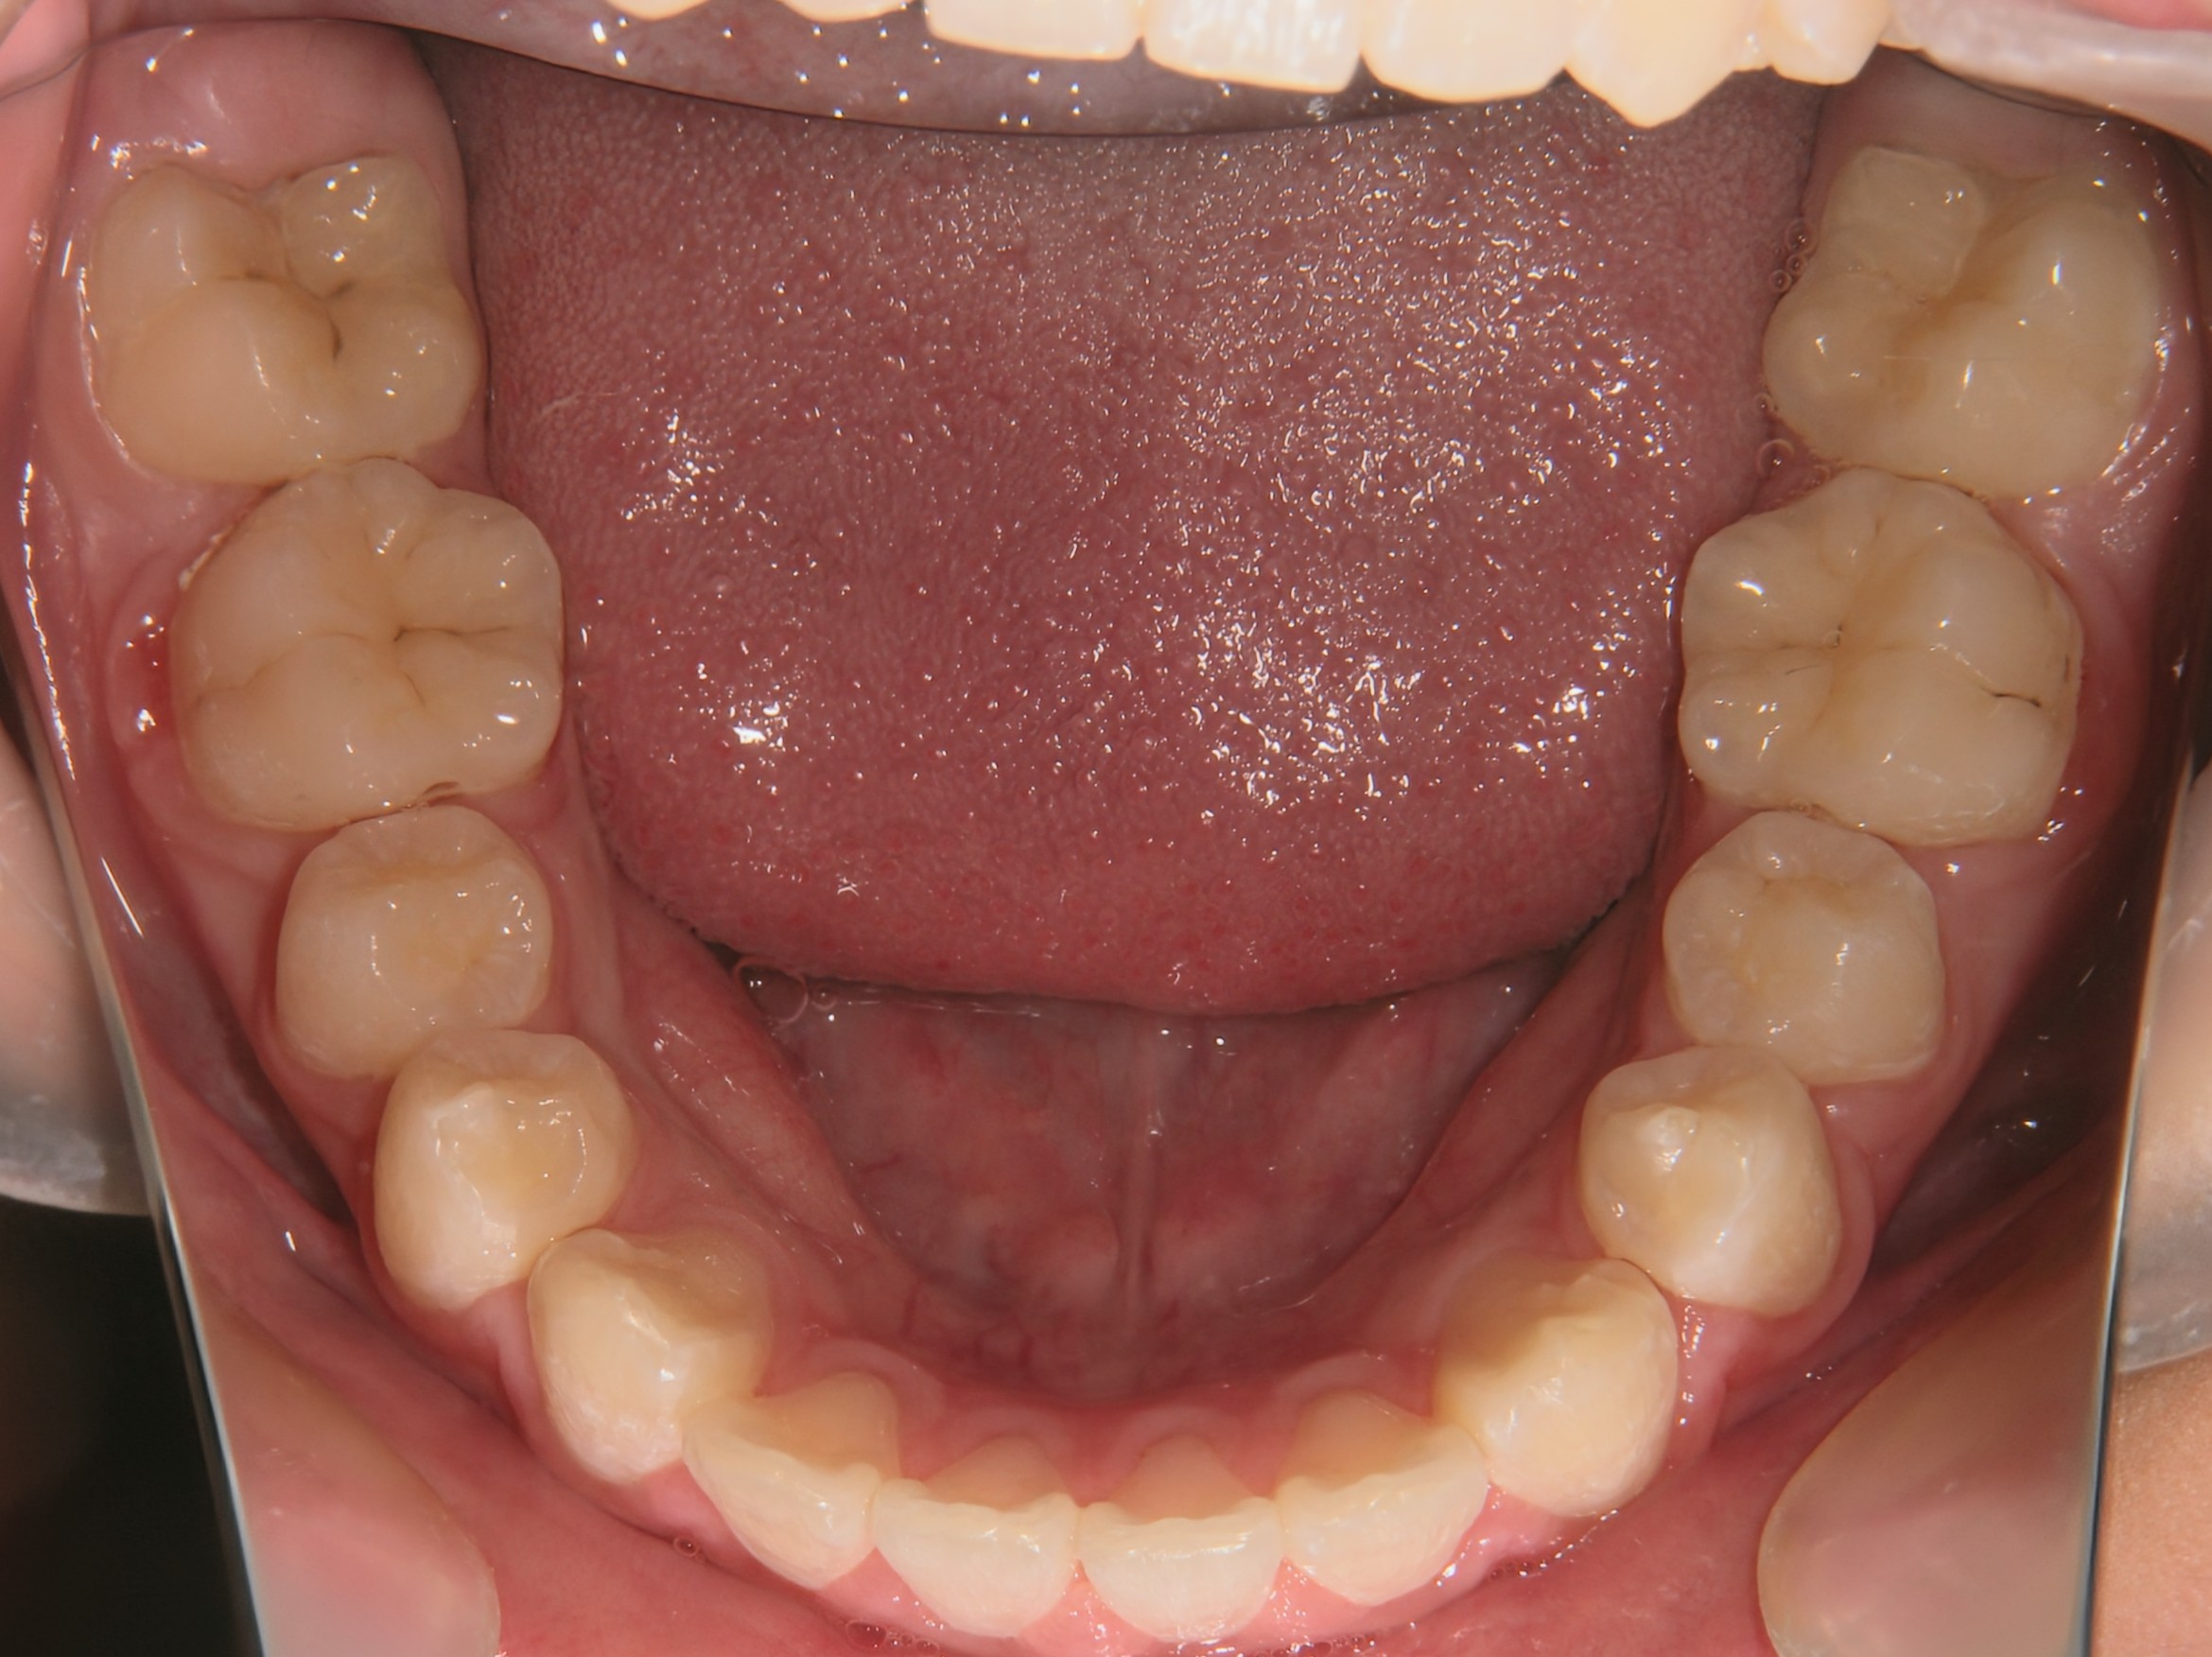

口腔内写真

開始年齢

13歳

主訴(患者様のお悩み)

残りの歯のデコボコを治したい

診断

上下顎軽度の叢生(上下の歯のデコボコ)

上顎右側犬歯低位(右上の八重歯)

治療方針

非抜歯矯正治療

全体的に装置を装着し、歯のデコボコや咬み合わせを治療

使用装置

表側矯正装置

治療期間の目安:約1年~1年半(保定期間を除いた期間)